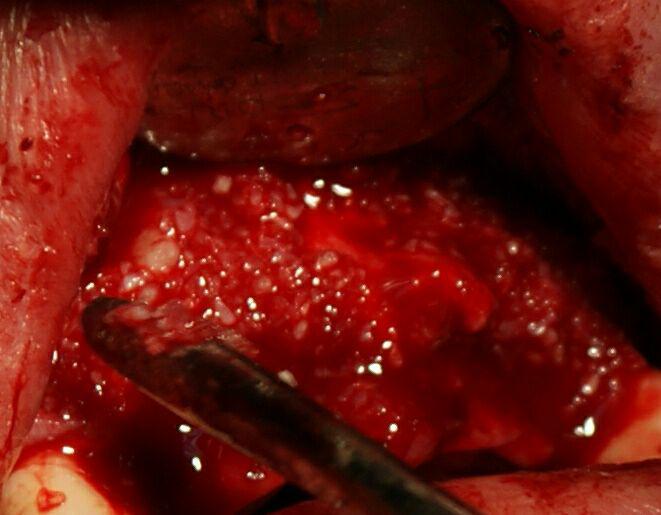

Residual gaps between the blocks and the underlying bone were filled with particulate allograft material, i.e. demineralized freeze-dried bone allograft (DFDBA) produced by the above-mentioned company (Figure 5).

Figure 5.Residual gaps filled with particulate allograft material.